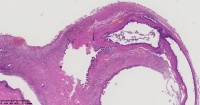

炎性息肉?潴留囊肿?腺体是否有问题?

性别

女

年龄

51岁

临床诊断

一般病史

宫颈赘生物

标本名称

图2

息肉。

稳妥起见最好做一做免疫组化。